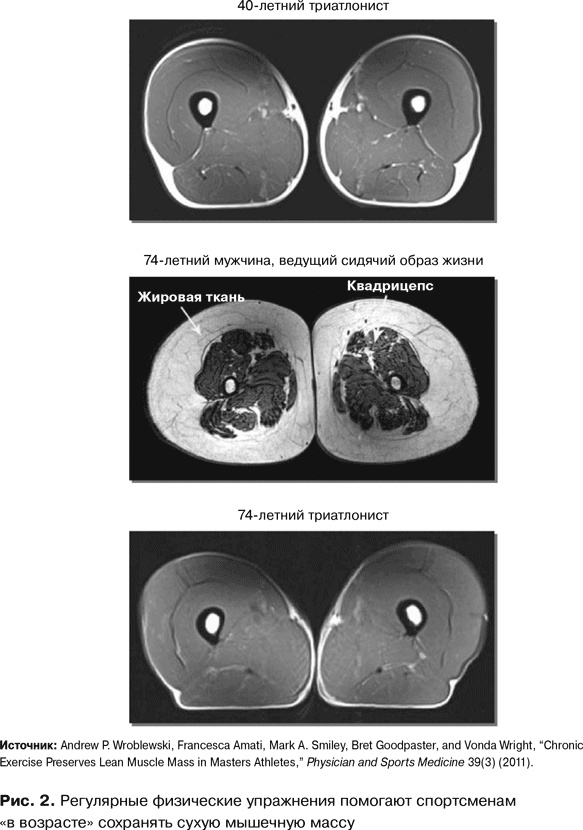

Что же происходит с мышцами, если вы регулярно и активно двигаетесь? Мы с коллегами решили ответить на этот вопрос, понаблюдав за немолодыми спортсменами-любителями, тренирующимися четыре-пять раз в неделю {8}. Благодаря снимкам МРТ я смогла отследить изменения в объемах сухой мышечной массы. Результат меня потряс.

Постоянная подвижность сохраняет сухую мышечную массу, предотвращает заплывание мышц жиром и потерю мышечной силы. Источник молодости существует, а волшебный эликсир – это подвижность! Но, как говорится, лучше один раз увидеть.

На рис. 2 представлен снимок бедра 40-летнего триатлониста. Похоже на кусок нежирной говядины. Мышцы в превосходном состоянии, мышца жиром не заплыла, подкожного жира практически нет. Далее мы видим снимок бедра 74-летнего мужчины, ведущего сидячий образ жизни. Совсем другая картина, правда? Мышцы развиты слабо, количество подкожного жира значительно, жир проник и в мышцы. Это скорее жирный ростбиф, чем постная говядина. А теперь взгляните на следующий снимок. Кульминационный момент. Мы видим бедро физически активного 70-летнего мужчины, триатлониста. Перед нами снова будто кусок нежирной говядины – отличное состояние мышц, совсем мало жира, что внутри, что вокруг. И – в качестве бонуса – видно, что квадрицепсы человека, живущего активной жизнью, с годами не теряют силы. В ходе моего исследования ни в одной возрастной группе до 60 лет не наблюдалось никакого статистически значимого расхождения в силе, а затем – никаких дополнительных различий вплоть до последней, 80-летней возрастной группы.